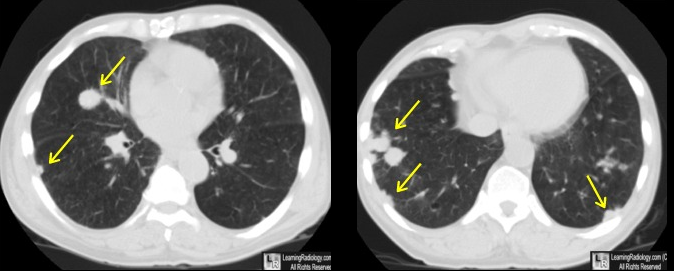

CT

- Nodules nécrobiotiques avec cavitations et prédominance sous-pleurale

- Plutot petits-moyens en taille (contrairement DD: Wegener)

- Complications: Pneumothorax